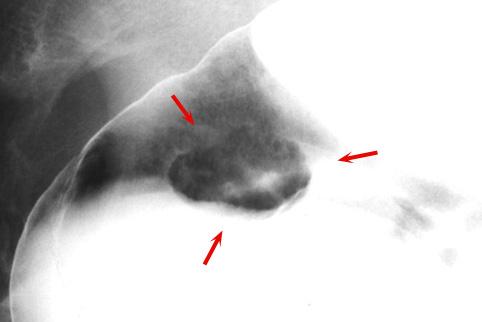

疾病(病理主体)的分类类癌肿瘤/

部位(按器官分)大肠/直肠

检查方法X线

肿瘤最大直径15~19